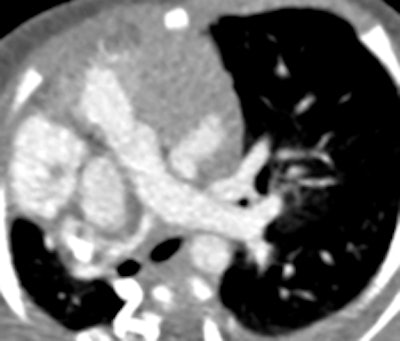

Prospective ECG-gated study on an unsedated free-breathing 2-month-old girl with an average heart rate of 122 beats per minute (bpm). The right pulmonary artery is hypoplastic (top left). An aortopulmonary collateral arising from the celiac axis supplies the right lung, as shown in the volume-rendered image (top right) and the maximum intensity projection image (bottom). All figures courtesy of Carolyn Young.